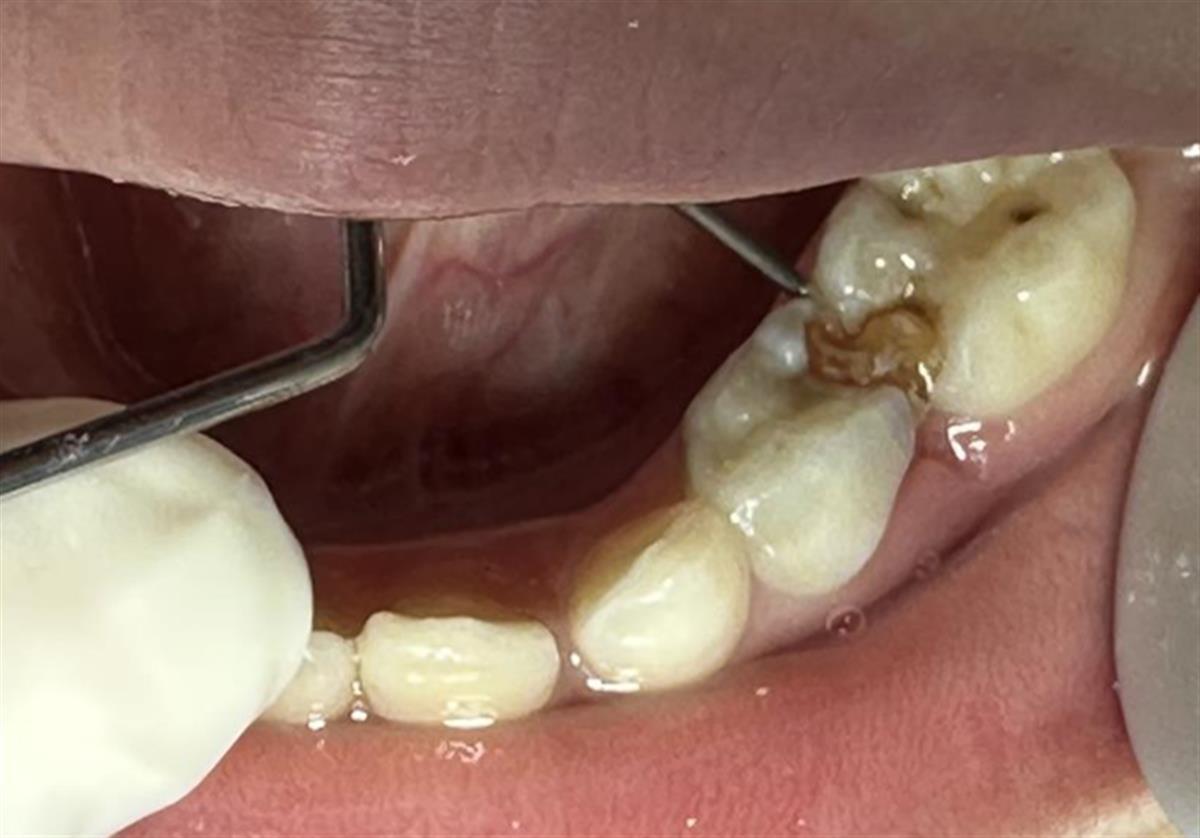

自行修补的牙齿(通讯员供图)

该院口腔科医生张雯接诊后,对团团的口腔状况进行了详细检查。医生发现,团团的牙齿正处于替牙期,烂洞的左下第一乳磨牙已严重松动,牙龈红肿。邻近的左下第二乳磨牙,则因补牙材料的连接,也出现晃动。